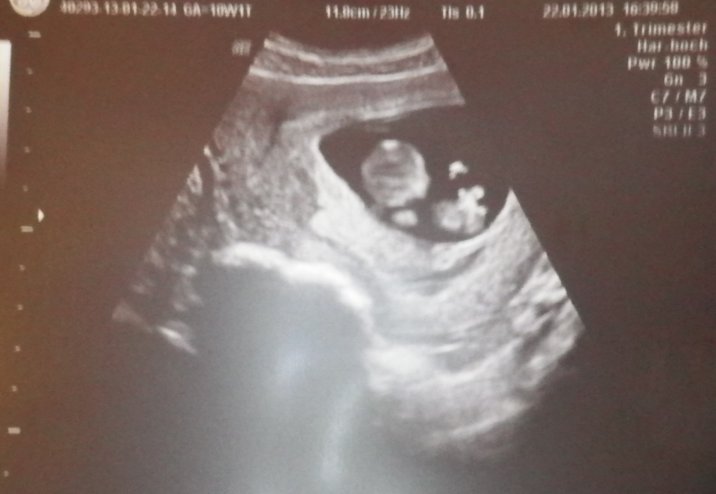

10週目にして始めてべいべーを見る。

上になってるほうが頭で、下が胴体。

離れっこ島みたいになってるのが手だって。

仰向けで丸まって寝てるの。

心拍もとくとくしてるの見れたし、背骨もできてるねって見せてもらった(;v;)

今3,7センチくらい。